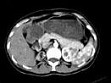

- 多项选择题女,35岁, 右侧腰部不适,CT增强扫描如图所示, 下列说法正确的是 ( )

A、右肾轮廓明显小于左侧,边缘光滑规则

B、左肾代偿性肥大

C、考虑为右小肾畸形

D、右肾完全无功能

E、考虑为右肾肾自截